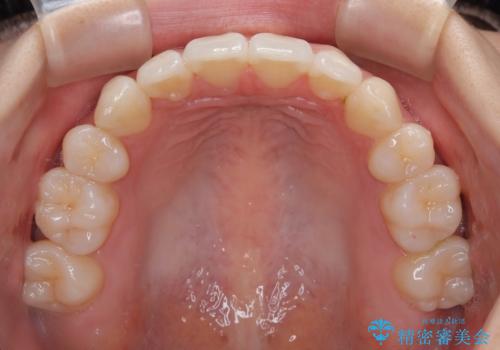

1. 抜歯矯正の軽度後戻りを解消 インビザライン矯正の治療前